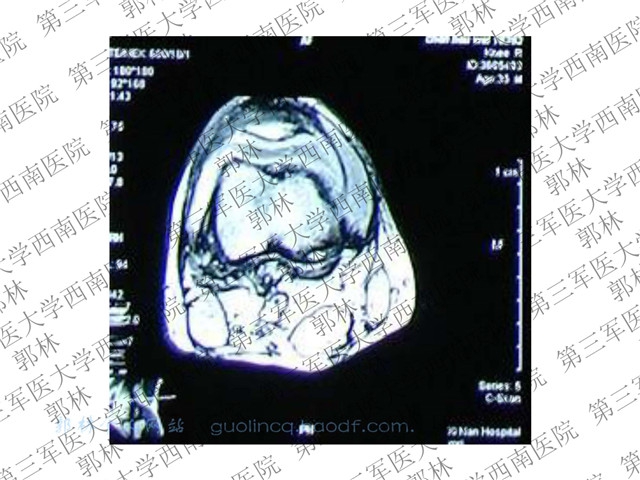

2015-02-28 文章来源:第三军医大学西南医院 郭林 我要说